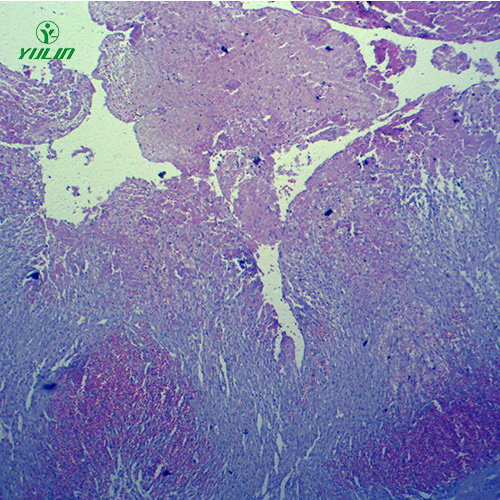

众所周知,人体局部血液循环障碍病理玻片需要在浙江显微镜下观察,但是很多用户不知道如何更好的使用人体局部血液循环障碍病理玻片。所以给大家讲解一下如何使用人体局部血液循环障碍病理玻片。

说到人体局部血液循环障碍病理玻片,我们都会想到实验课上做的一些实验。我们都知道人体局部血液循环障碍病理玻片可以帮助我们更好地学习生物。然而,在制作人体局部血液循环障碍病理玻片的过程中,不可避免地会出现一些问题。这里了解一下制作过程中会遇到哪些问题。

我们都知道人体局部血液循环障碍病理玻片对研究生物细胞的重要性,我们都知道一旦出现问题,就会对研究结果产生严重的后果。你知道影响人体局部血液循环障碍病理玻片检测的因素有哪些吗?如果你不知道,请跟随我们了解一下。